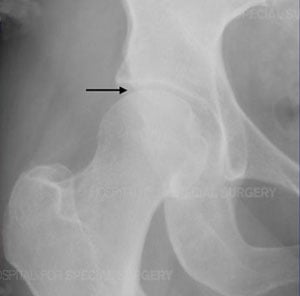

Anteroposterior (front-to-back) X-ray of a normal hip joint. The joint space is uniformly open, indicating that the cartilage is healthy (arrow).